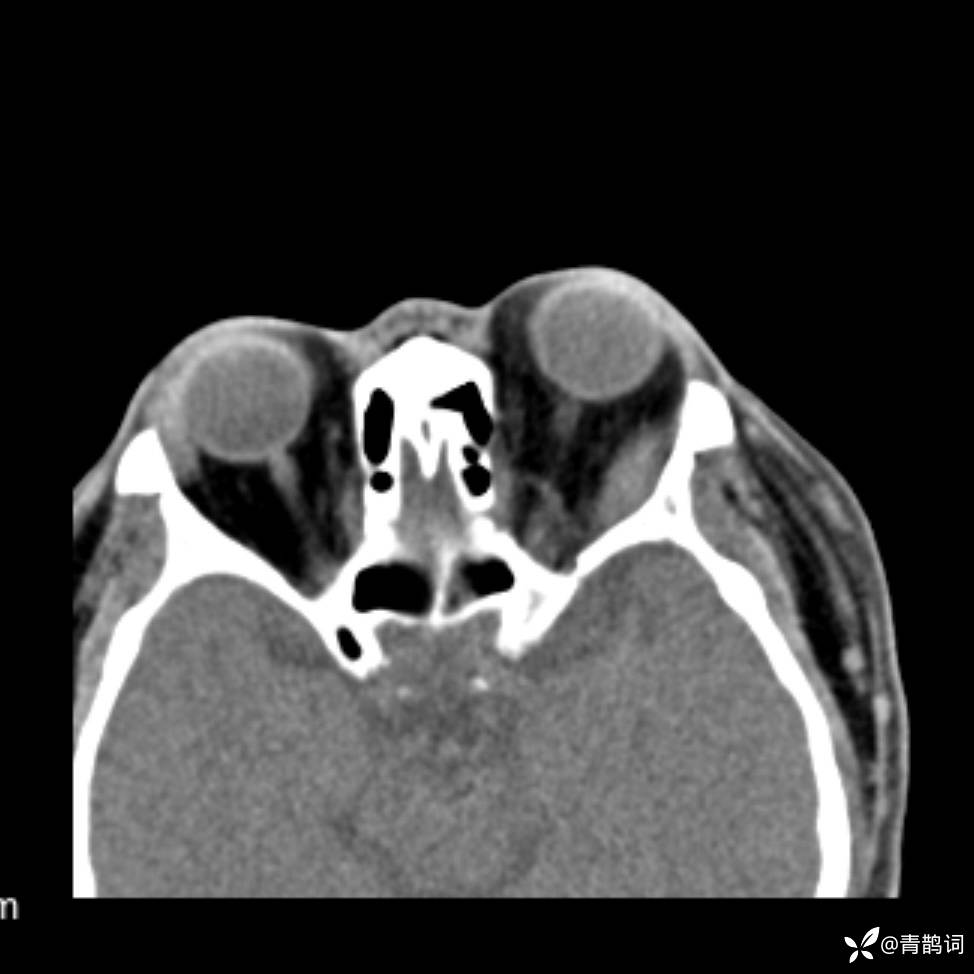

患者年龄:30岁。

患者性别:男。

简要病史:左颜面部肿胀2年,反复咳嗽咳痰,逐渐加重。

结合病史及影像学表现,期待评论区各位老师各抒己见~

木村病 (14)